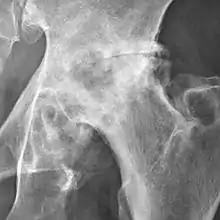

Osteoarthritis of the hip joint may also be graded by Tönnis classification. There is no consensus whether it is more or less reliable than the Kellgren-Lawrence system.[8]

Severe (Tönnis grade 3) osteoarthritis of the hip.

Tönnis classification[9]

Grade Description

0No osteoarthritis signs

1Mild:

• increased osteosclerosis

• minor joint space narrowing (normal joint space is at least 2 mm at the superior acetabulum)[7]

• no or minor loss of head sphericity

2Moderate:

• small bone cyst

• moderate joint space narrowing

• moderate loss of head sphericity

3Severe:

• large bone cysts

• severe joint space narrowing, or joint space obliteration

• severe deformity of the head